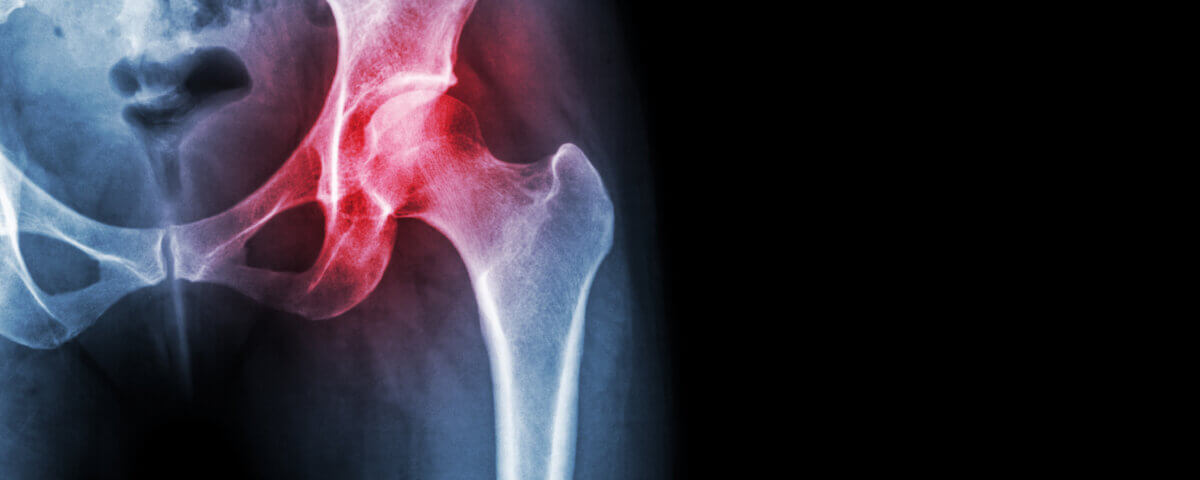

Hip fractures happen in many different situations such as wrecks, side impacts, bike accidents, slips or falls at business premises or on uneven ground. The impact is often severe: hospitalization, surgery, physical therapy, and a recovery period that affects mobility. The injury is not just physical, it carries emotional, mental, and financial burdens when someone cannot move freely or get back to their daily routines.

Not all hip injuries are the same. The type of fracture or damage will determine recovery time and when driving becomes safe:

- Femoral neck fractures often need screws or pins, sometimes partial hip replacement

- Intertrochanteric fractures generally require surgical hardware and longer physical therapy

- Acetabular fractures involve damage to the hip socket and often call for more complex surgery

- Hip dislocations can be very painful and may lead to recurring issues if not managed properly

Each of these injuries carries a different timeline for healing and regaining strength, flexibility, and control.